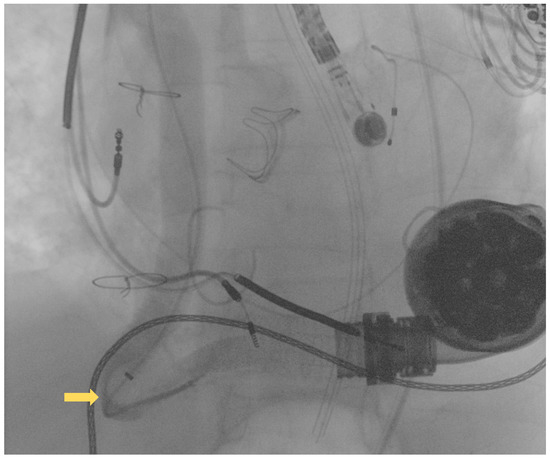

A 69 year old male with advanced HF (LV ejection fraction: 25%) due to severe familial dilated cardiomyopathy was admitted to our emergency department, complaining of severe dyspnea and asthenia. The symptoms had started one week previously and had progressively worsened. Three years before, the patient had undergone surgical aortic valve replacement for severe aortic regurgitation (Inspiris Resilia TM 26 mm, Edwards Lifesciences LLC, Irvine, CA, USA) combined with a tricuspid valve ring annuloplasty (Contour 3D TM, Medtronic, Dublin, Ireland) and followed by LVAD implantation (HeartMate III TM, Abbott, NC, USA) as a destination therapy. One year after this, the patient experienced LVAD failure caused by a proximal thrombosis of the outflow graft, which was effectively treated with a percutaneous intervention using a 10 × 59 mm balloon-expandable covered stent (ADVANTA V12-8 Fr compatible covered stent, Getinge AB) [8]. In Figure 1A,B pre- and postprocedural angiographies of the first procedure are shown.

Figure 1.

(A) preprocedural angiography of the first outflow graft obstruction episode (yellow arrows highlighting the kinking site and proximal thrombosis location); (B) result following the first percutaneous intervention.